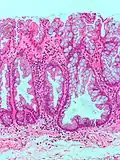

| Hyperplastic polyp | Colorectal (unless otherwise specified) | Serrated unbranched crypts | if polyps are more than 100 | ![]() |

Serrated polyposis syndrome |